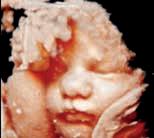

3D és 4D ultrahang elérhető a Budai Magánorvosi Centrumban!

Az elkészült képeket odaadjuk pendrive-on, de nyomtatott képet is adunk mellé.

Az apukákat, nagyszülőket, de akár a nagytesókat is örömmel látjuk a vizsgálaton!

A 3D funkciónak köszönhetően térbeli képet kaphatunk a magzatról, a 4D funkció segítségével szemtanúi lehetünk a baba mozgásának is.

Egy rendkívül modern, magas felbontású Samsung ultrahang készülékkel dolgozunk, mely éles képet ad a magzatról, a fekvésétől és az anatómiai viszonyoktól függően.

Ha szeretne valamely hozzátartozójával a babamozi élményében részesülni, kérjenek időpontot bátran.